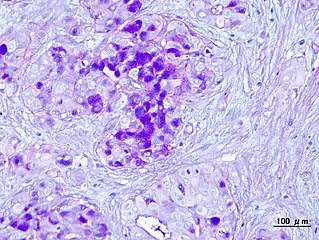

| Micrograph of a mucoepidermoid carcinoma. FNA specimen. Pap stain. | |

In terms of diagnosis we find that histological staining, radiological imaging and molecular diagnostic features all play a role in the evaluation[1] This tumor is not encapsulated and is characterized by squamous cells, mucus-secreting cells, and intermediate cells.[7]